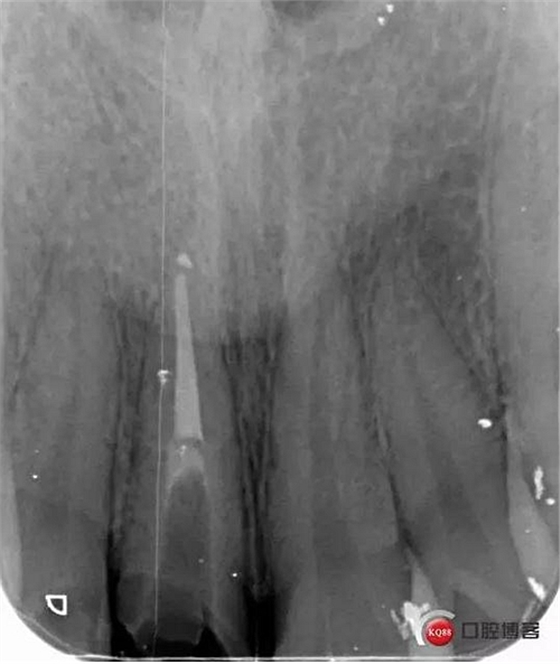

看起來有點(diǎn)頭痛哈,拍片檢查

牙根長(zhǎng)度比較號(hào),根充完善。這張片子也可以看出,為什么上次脫落了,樁的深度不夠,而且明顯樁根樁道不匹配,打的樁都沒有到位。